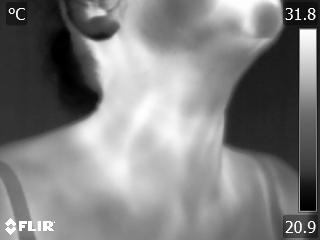

Grayscale palette converts the temperature matrix into a gray scale image by mapping the temperature values into a numerical range of 0 to 255, which represents the intensity or brightness of the gray color. Variation in the shades of gray allows one to study the variations in the heat patterns. Cooler temperature regions appear darker or closer to black, while warmer temperature regions appear lighter or closer to white. This grayscale representation allows for a straightforward visualization of temperature differences without the distraction of color information. Grayscale palettes are commonly used for visualizing structural details, such as vessels, bones or tissue boundaries.